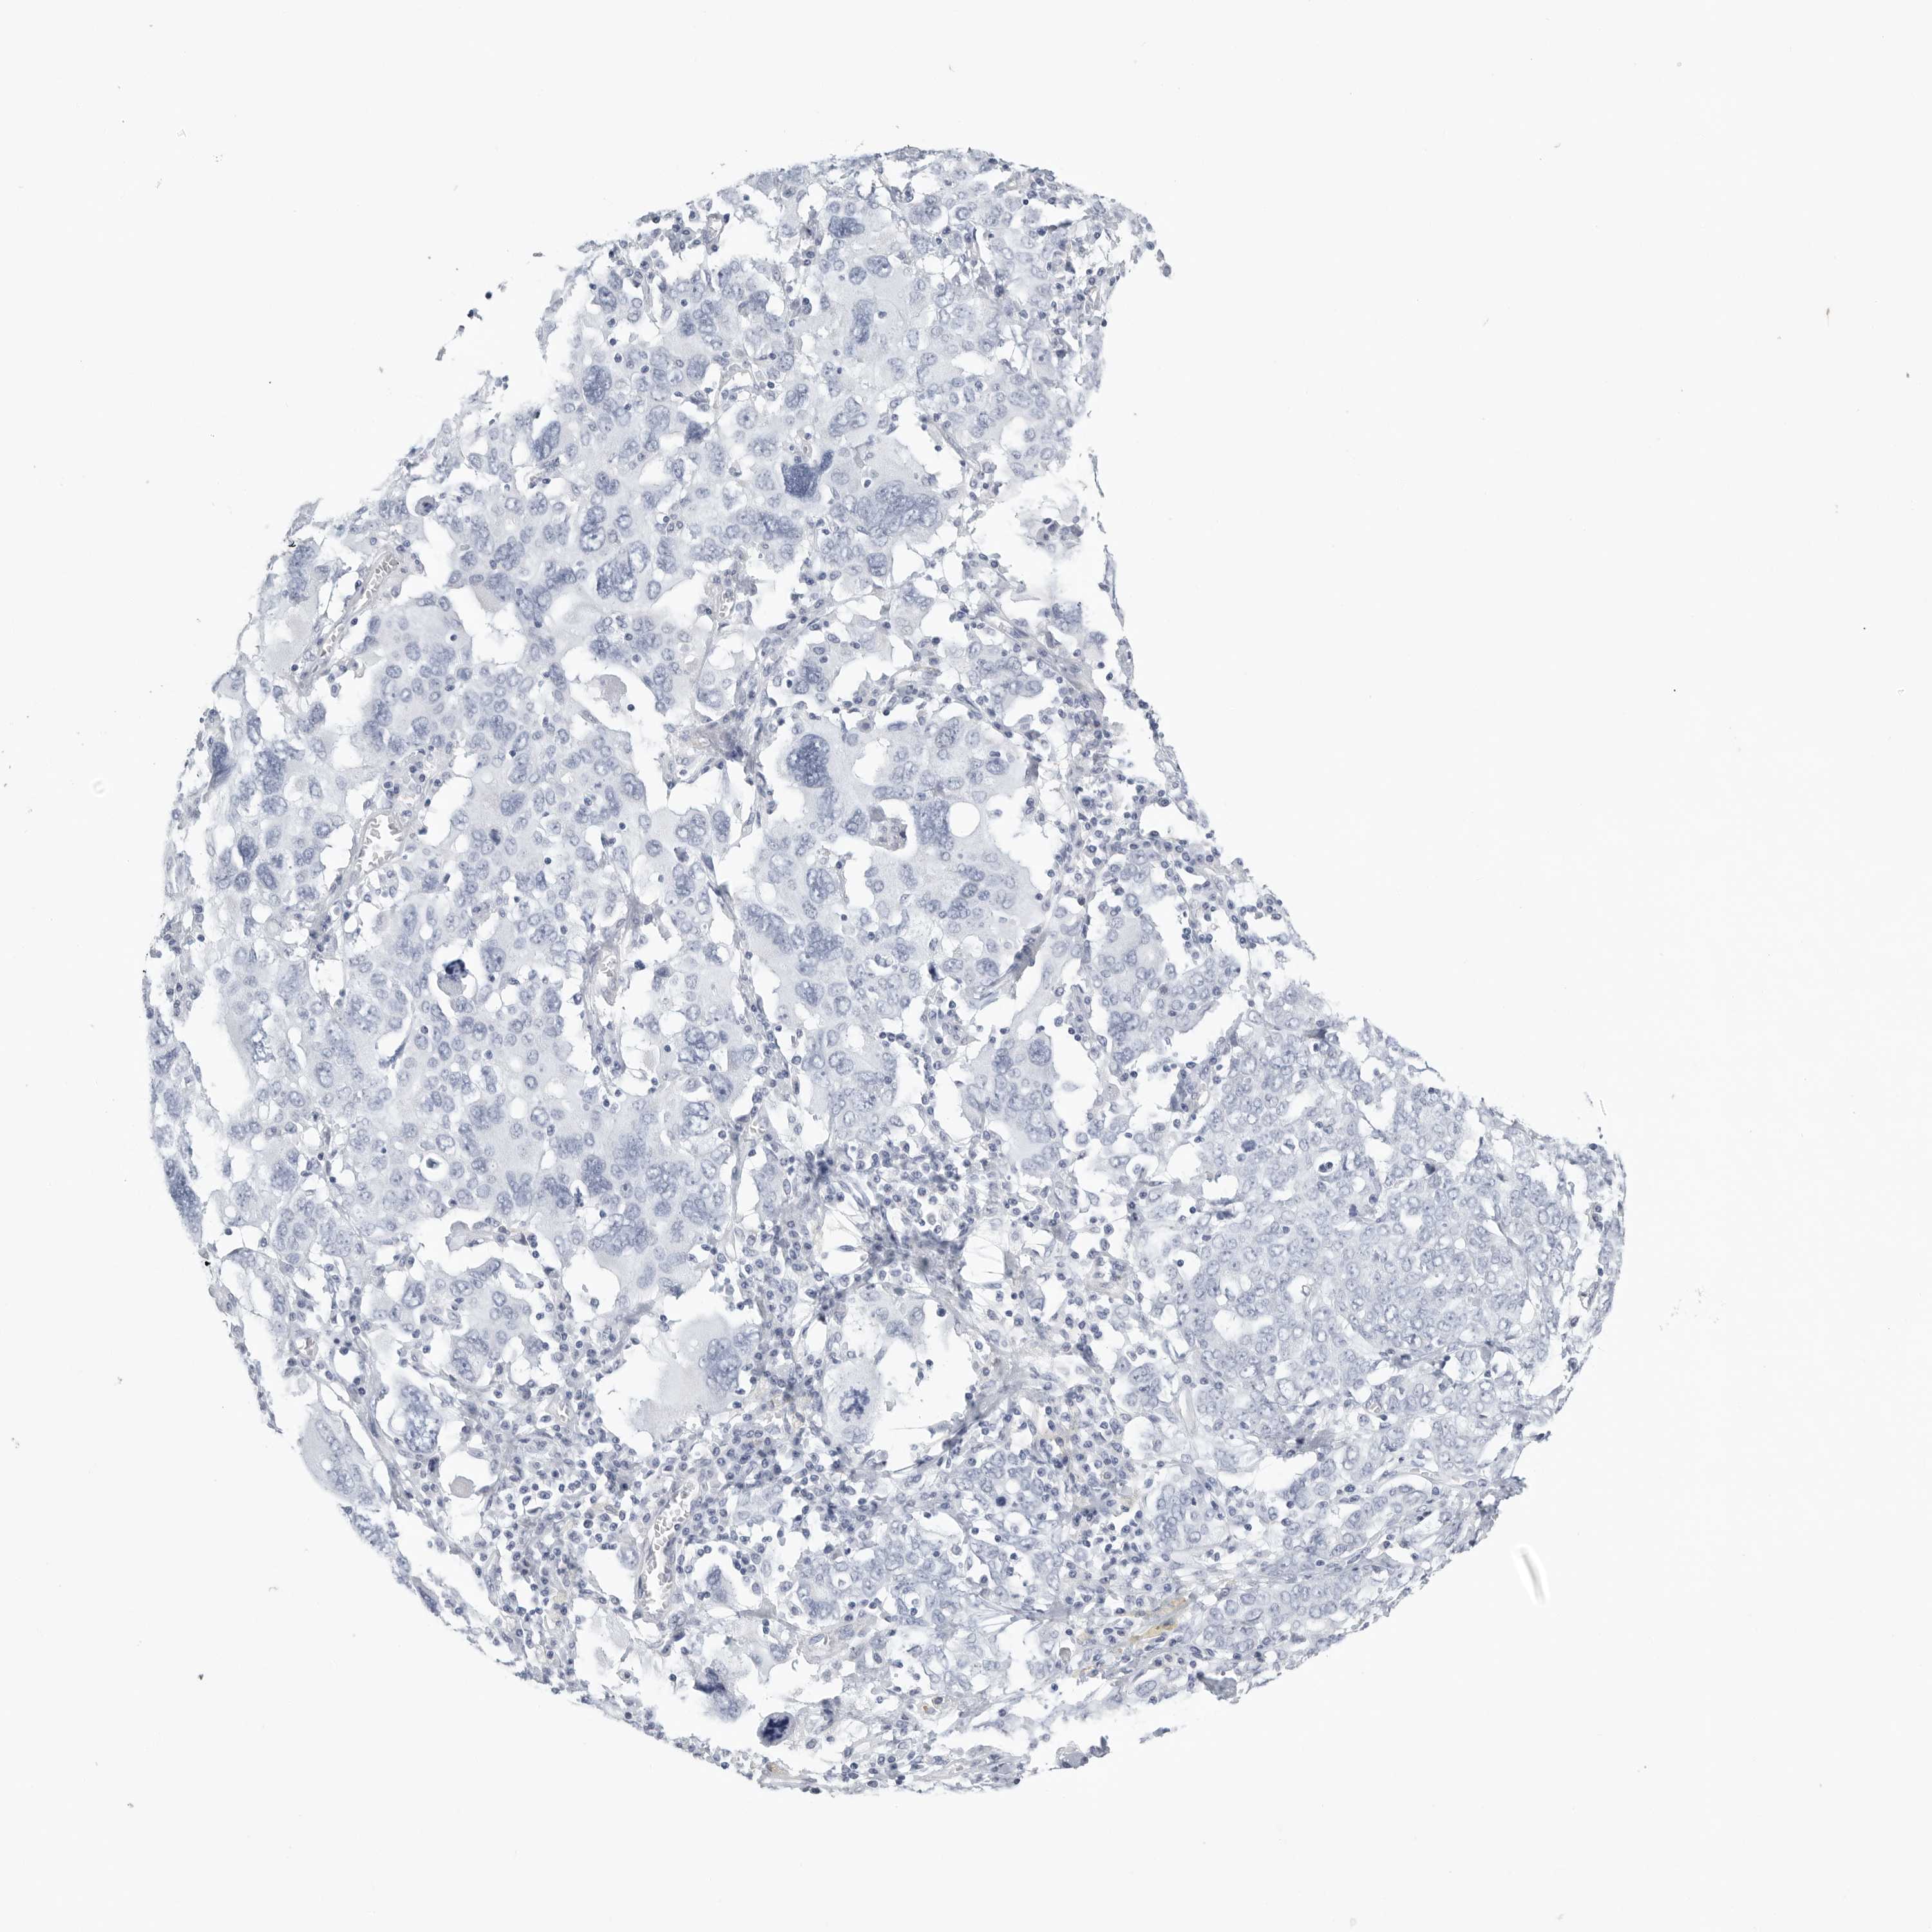

OVARIAN CANCER - Protein expressioni

A mouse-over function shows sample information and annotation data. Click on an image to view it in a full screen mode. Samples can be filtered based on level of antibody staining by selecting one or several of the following categories: high, medium, low and not detected. The assay and annotation is described here.

Note that samples used for immunohistochemistry by the Human Protein Atlas do not correspond to samples in the TCGA dataset.

Antibody stainingi

Antibody staining in the annotated cell types in the current human tissue is reported as not detected, low, medium, or high, based on conventional immunohistochemistry profiling in selected tissues. This score is based on the combination of the staining intensity and fraction of stained cells.

Each image is clickable and will lead to virtual microscopy that enables deeper exploration of all samples and also displays staining intensity scores, fraction scores and subcellular localization as well as patient and tissue information for each sample.

Antibody HPA027134

Antibody HPA027150

Antibody HPA029859

Antibody CAB022343

Staining

High

Medium

Low

Not detected

Intensity

Strong

Moderate

Weak

Negative

Quantity

>75%

75%-25%

<25%

None

Location

Nuclear

Cytoplasmic/membranous

Cytoplasmic/membranous,nuclear

Cystadenocarcinoma, serous, NOS

Carcinoma, endometroid

Cystadenocarcinoma, mucinous, NOS

Carcinoma, NOS